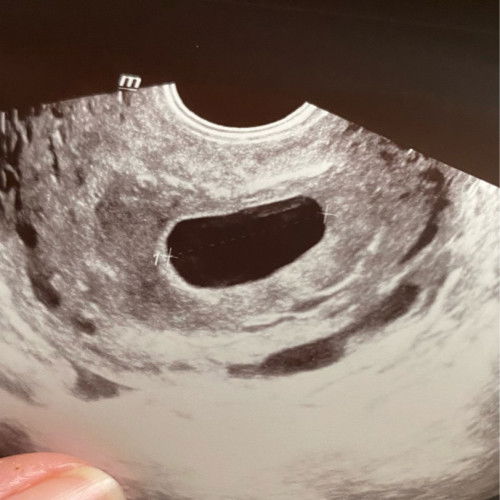

Hi mommies . Smlm sy ada brownish + slightly reddish . Sy terus ke klinik utk cek . Lepastu doc scan baby tkda . Hanya kantung . Kalau ikut kiraan, dh 7w+ .. Tp sy pelik masa keluar cecair brownish + reddish tu tak sakit lgsg . Doc cek jantung pun tk dgr apa2 . So doc suruh pergi GH nanti refer o&g . Ada sesiapa berpengalaman mcm ni ? Mmg betul2 gugur ke / masih awal & ada harapan ?